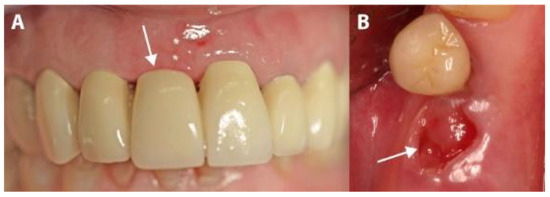

2.2. Surgical Procedure

2.3. Measurements and Prosthetic Restoration